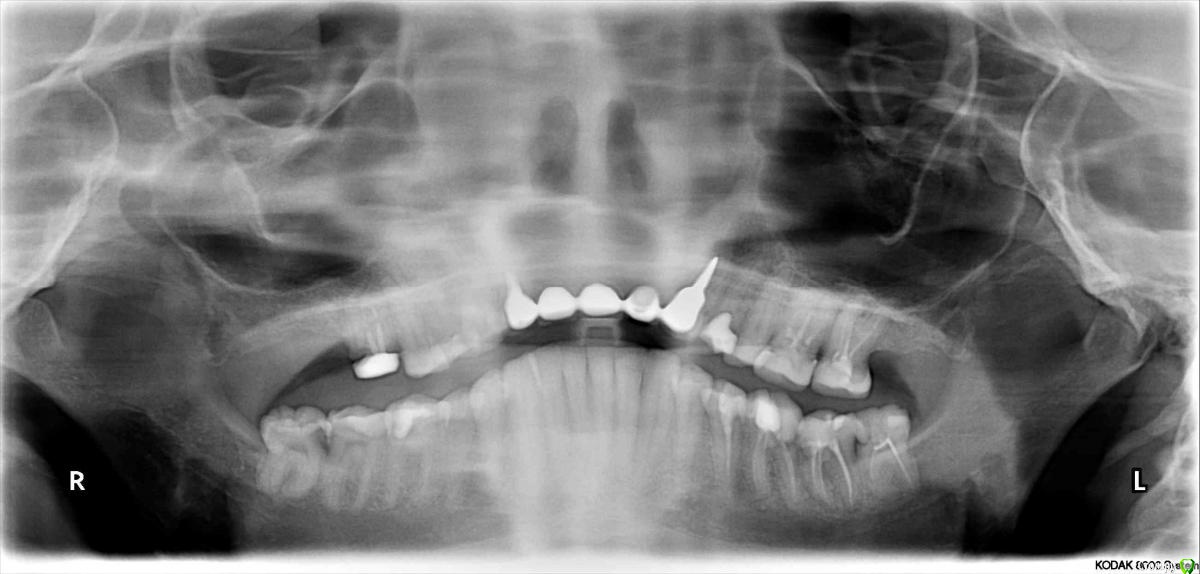

Yashika Опубликовано 25 декабря, 2015 Поделиться Опубликовано 25 декабря, 2015 (изменено) Уважаемые доктора, у меня очень короткий вопрос т.к. я не понимаю, продолжать ли мне искать доктора или я ищу чего-то невозможного На передних верхних зубах стоит мост металлокерамика (вкладки кобальт-хром) на 2 опорных. Сзади ушла десна, образовались карманы, иногда кровит. ХОЧУ ЗАМЕНИТЬ КОНСТРУКЦИЮ с учетом текущей ситуации. Сталкиваюсь с тем, что второй протезист отказывается распиливать коронки Говорят, вкладки массивные и стенки довольно тонкие, боятся в процессе сломать корни. Но я вроде бы не прошу ломом выдрать вкладки, только снять коронки. Отказываются! Говорят "ходи так пока сами не расцементируются"! А, если оно 10 лет еще не расцементируется? Подскажите, я прошу действительного невозможного? Металлокерамику разве нельзя распилить и заменить, не выдирая вкладки при этом? На снимках орто и (простите это максимум, как я могу раззявить рот и моей камеры), но думаю, примерно понятно, где ушла десна и почему хочу это все снять. Спереди все нормально, карманы только сзади. Изменено 25 декабря, 2015 пользователем Yashika Ссылка на комментарий